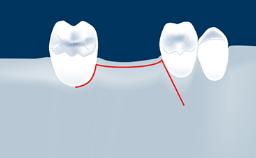

• define the manufacturing process of digital guides for SFE

• explore the intraoperative use of digital guides in SFE